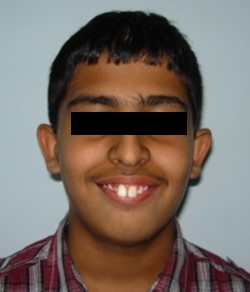

A 14-year-old male presented with severe crowding and forward placement of the maxillary and mandibular incisors. Inherited growth pattern could have been the most possible etiological factor.

Extraoral assessment. (Figure 1a,Figure 1b,Figure 1c).

Figure 1c.Pre-treatment extra-oral-Smiling

The patient had a leptoprosopic face, convex profile, posterior divergence, incompetent lips, clinical high mandibular plane angle, complete maxillary incisor display on smiling with no signs of temporomandibular joint dysfunction.